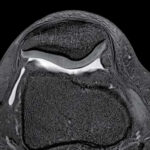

MRI is a versatile imaging technique that can be used to examine various parts of the body, including the brain, spine, joints, abdomen, and pelvis.

It is particularly useful for visualizing soft tissues like organs, muscles, tendons, ligaments, and the central nervous system. Unlike X-rays or CT scans, MRI does not use ionizing radiation, making it a safer option for many patients, including pregnant women and children. MRI is a valuable tool in modern medicine, providing non-invasive and detailed imaging that helps healthcare professionals make accurate diagnoses and develop effective treatment plans for patients.